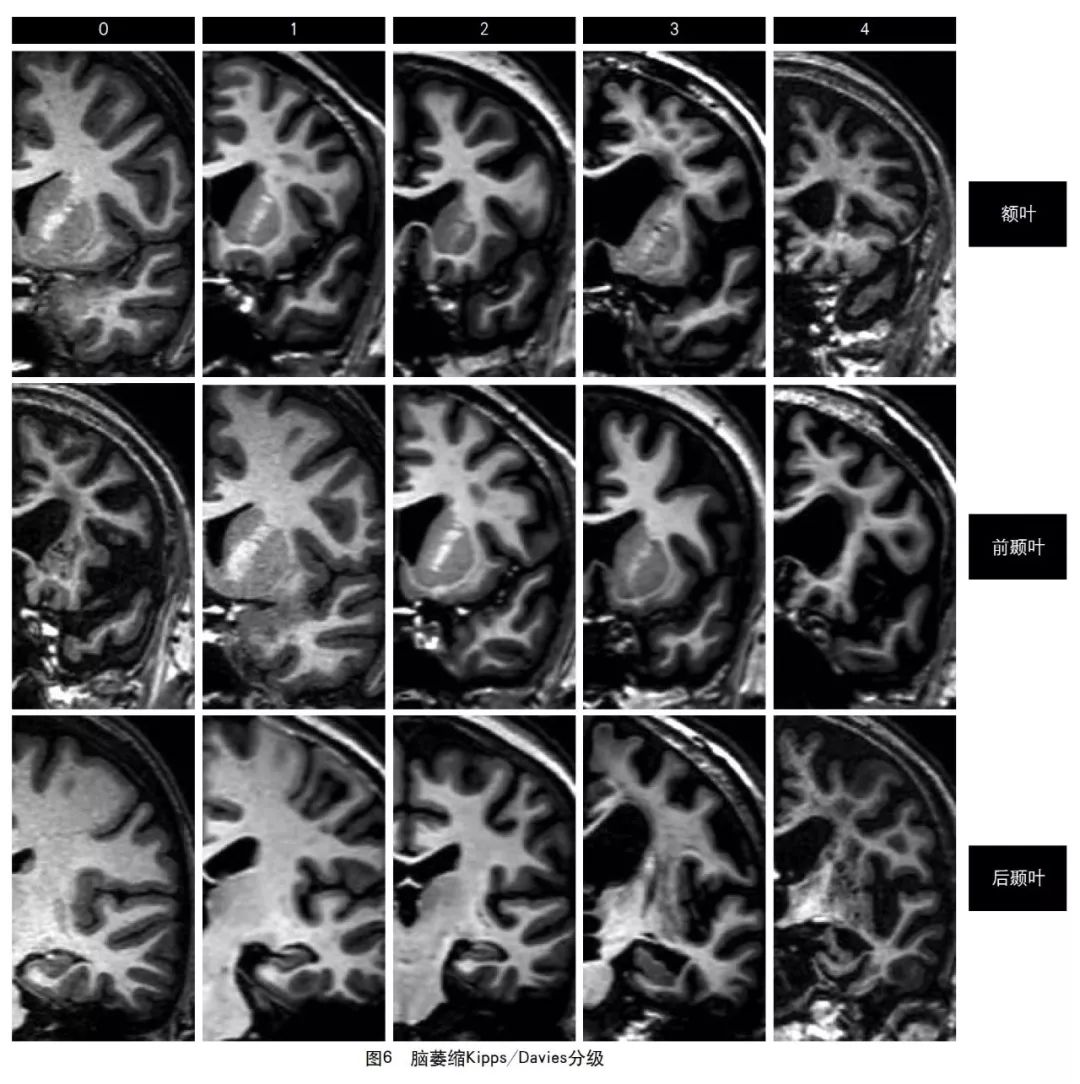

2013年的共识指南将脑萎缩定义为与特定的局灶性损伤,如脑外伤或脑梗死无关的脑容积减少。脑萎缩可以是广泛的或局部的(如特定的脑叶或海马等特定区域),可以是对称或不对称的,亦可以是组织选择性的(如发生在白质等某一特定组织层)。目前不同部位的脑萎缩有相应的诊断标准,全脑皮层萎缩分级用于评价全脑(图3);内侧颞叶萎缩分级主要评价颞叶内侧,重点是海马(图4);Koedam分级主要评价顶叶,尤其是扣带回和楔前叶(图5);Kipps/Davies分级主要评价额颞叶(图6)。推测脑组织减少是由脑沟(周围)和脑室(中心)的脑脊液空间相对于颅内容积扩大所引起的。